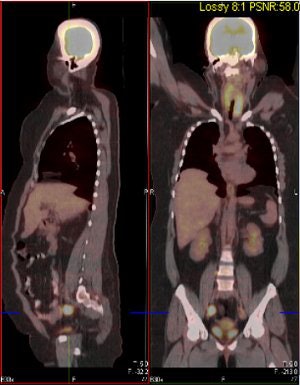

| Above and below, representative images of a 39-year-old patient, currently undergoing treatment, with FIGO stage IB2 squamous cell carcinoma of the cervix. Pretreatment FDG-PET/CT identified an FDG-avid cervical tumor mass plus bilateral iliac and right common iliac metastatic lymphadenopathy. Images courtesy of Dr. Julie Schwarz, Ph.D. |

Twenty-five patients with advanced-stage cervical cancer were included, all of whom were treated with chemoradiation. Whole-body FDG-PET scans were done and co-registered with CT scans. Twenty-eight pretreatment tumor biopsies were done, and pathologic review confirmed the presence of invasive cancer in 26 of 28 cases.